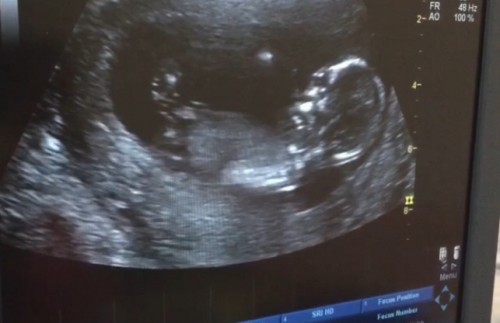

หมอบอกน้องตัวยาวใหญ่

วันนี้ไปซาวมาค่ะ ปกติครั้งก่อนๆจำนวนวีคบวกลบไม่เกิน 3วัน วันนี้ไปซาวอายุวีคในสมุดชมพูที่หมอเขียนกับในแอปคือ13w3d แต่ใบซาวคือ15w2d ใครเคยเจอแบบนี้บ้างคะ สงสัยน้องตัวใหญ่ไปแน่ๆเลยค่ะ 😂 (ว่าแต่แบบนี้จะยึดอายุวีคที่เท่าไรกันคะ)

ยึดตามหมอค่ะ